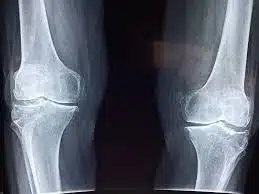

La menace silencieuse pour votre squelette

Un aspect méconnu des sodas, particulièrement des colas, concerne leur influence sur la robustesse de notre structure osseuse. Le danger ne réside pas dans un composant spécifique, mais plutôt dans le fait qu’ils remplacent souvent des boissons riches en calcium essentielles, comme le **lait ou les alternatives végétales enrichies**. Pour les adolescents et jeunes adultes, cette substitution peut compromettre l’édification d’une **masse osseuse solide**. Chez les adultes, elle peut participer à une **détérioration progressive** de la densité osseuse au fil du temps.